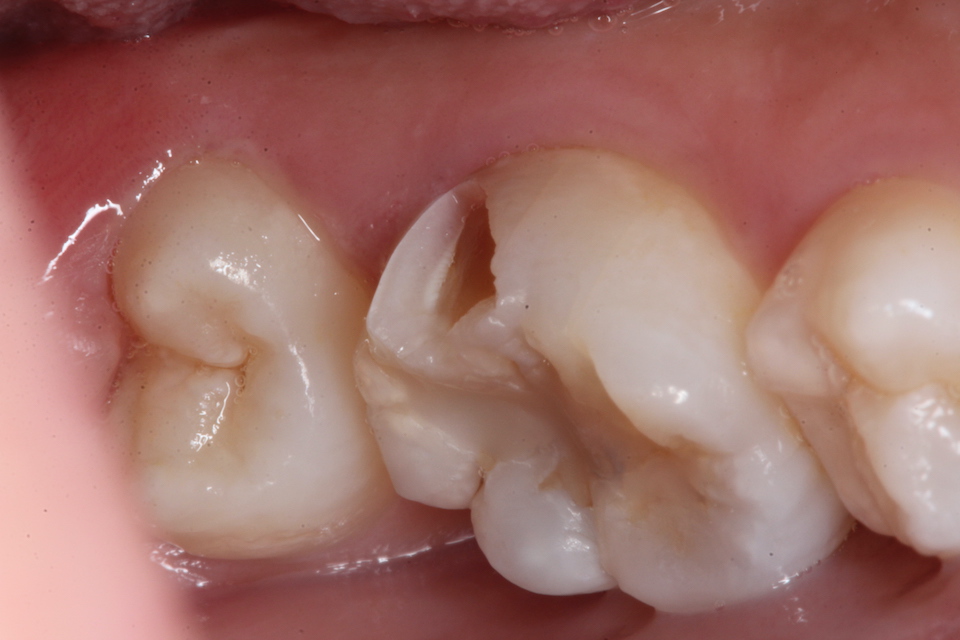

現在14歳女子、右下6、咬合面カリエス、咬合性外傷(食いしばり)、自覚症状なし

元々咬合面に深い溝や窩が歯の発生の過程でできることがあるのだが、そこから象牙質とエナメル質との間のイオン化傾向(自然電位)の差と虫歯の穴の中とその外部の間の酸素濃度差による起電力により虫歯が進行するタイプだ。

さらに外傷性咬合により微細なクラックがエナメル質に入り、虫歯の進行を助長する。

この子は2年後に象牙質の虫歯の進行によりエナメル質が欠けたので再治療した。内部の象牙質がほとんどなくなっているので、過大な咬合力に耐えられない。どうしたものか。。

・・突然歯が欠けたということでやってきた。内部の象牙質は虫歯になっていてプロセスチーズくらいの柔らかさになっていた。多数のクラックが見えると思う。

破折面を見てみると面白いことがわかる。内側から狐色の軟化象牙質(虫歯)、白い脱灰(腐食)が始まっているエナメル質、外側の半透明層が健全なエナメル質だ。なぜこうなるのか?現在の歯科医学の水準では説明が付かない。電気化学的になら説明ができるが、ちょっと眠たくなってきたので、日を改めて。